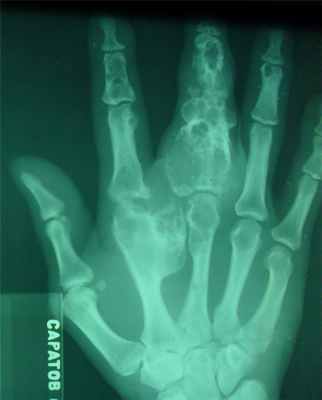

Прямая рентгенограмма таза и тазобедренных суставов.

Определяется резкая деформация тазового кольца. Правый тазобедренный сустав в норме. Выраженные изменения в левом тазобедренном суставе: суставная впадина углублена, суставная щель не прослеживается, головка деформирована с множественными очагами деструкции. Регионарный остеопороз, атрофия бедренной кости. Левосторонний туберкулезный коксит.